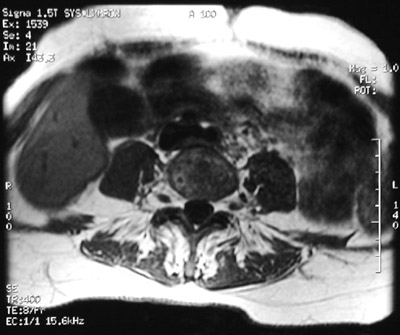

The rounded lucency seen here in a vertebral body with T1 weighted MRI scan is one focus of plasma cells in a case of multiple myeloma. This patient had lesions in multiple sites. Another lesion is seen below with T2 weighted MRI scan.